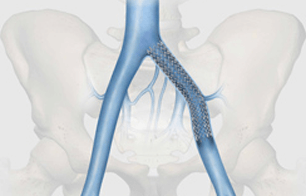

Bloomington, Ind. — Following Health Canada approval, Cook Medical made the Zilver Vena Venous Self-Expanding Stent available to physicians across Canada at the 2012 Annual Meeting of the Canadian Society for Vascular Surgery. Designed to restore blood flow in obstructed iliofemoral veins, Zilver Vena provides physicians with a tool designed specifically for stenting obstructed iliofemoral veins. This condition can arise for various reasons, including post-thrombotic syndrome in deep vein thrombosis (DVT) patients.

Built on Cook’s established line of Zilver stents, the Zilver Vena stent is a flexible, self-expanding stent made with“shape memory” nitinol. Zilver Vena was developed to address a challenging clinical issue, the need to establish and maintain blood flow in obstructed iliofemoral veins.

The stent provides flexibility, consistent radial force, and continuous stent-to-vein wall apposition from end to end. Zilver Vena is currently available in 14 and 16 mm diameters and 60, 100 and 140 mm lengths to enable precise placement, and is compatible with 7 Fr sheaths and 9 Fr guiding catheters.